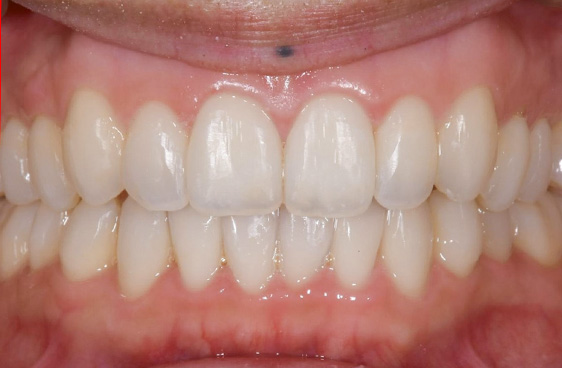

- 症例1

施術名:マウスピース矯正

プラン:湘南マウスピース

施術の説明:ご自身の歯の形に合わせてオーダーメイドの目立たないマウスピースを制作し、歯を移動させることで徐々に歯並びを改善させる治療法です。

施術の副作用(リスク):疼痛・咬合時痛が生じる可能性があります。また使用途中でマウスピースが緩んだり、外れやすくなるほか、割れたり壊れたりすることがあります。

施術の価格: 208,000円~953,000円